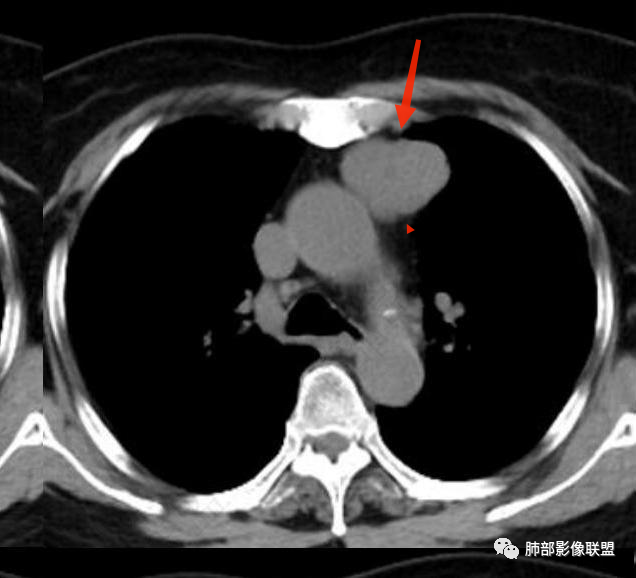

前上纵隔偏左侧实性病灶,边界清楚,边缘彭隆,浅分叶,内部密度均匀,未见钙化、脂肪密度,周围脂肪间隙清晰。

包膜完整,纤维分隔,结节感明显

平扫密度较均匀,增强渐进性不均匀强化,内见低密度纤维分隔。未见肿大淋巴结。未见胸腔积液。

肿块边界清楚,低密度纤维间隔,未见侵犯转移及增大淋巴结,多见于胸腺瘤AB型

—平扫密度不高,加之缺乏与颈部甲状腺解剖关联性,胸腔内甲状腺肿可能性较小。

—强化程度及强化方式不支持常见的血管瘤及巨淋巴结增生症(CD)。

—患者血压高,应当排除副节瘤可能。病灶未见坏死区,且发生于纵隔的嗜铬性副节瘤罕见。